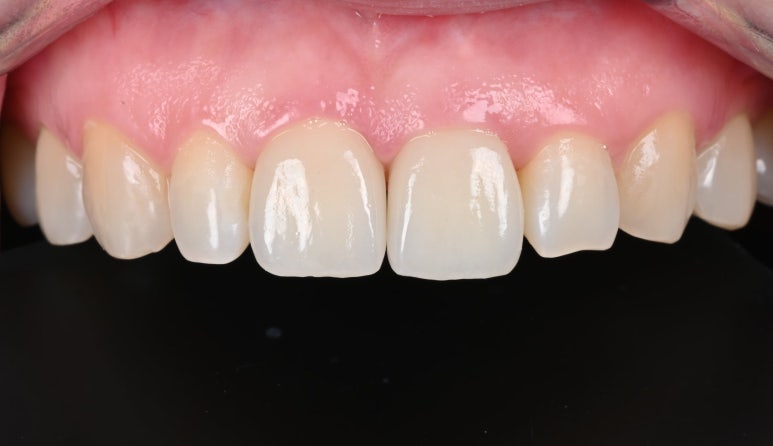

완성된 크라운

5. 최종 크라운 장착

새로 제작된 크라운을 장착합니다.

환자분께서 색상과 모양에 만족해하셔서 특별한 수정없이

치료를 마무리할 수 있었습니다.

25.09.11 치료 후